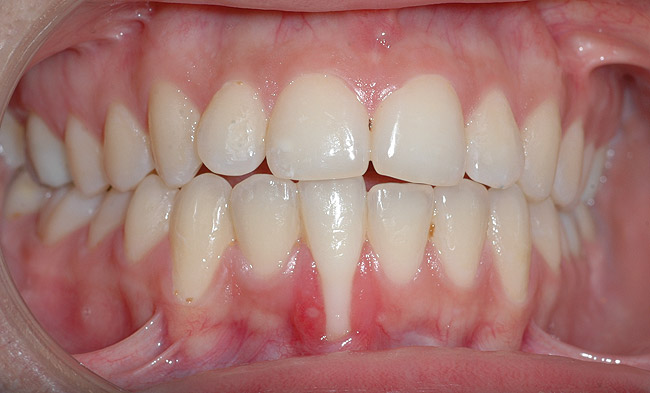

Case Report

A 19-year-old female complaining of gingival recession in the lower right central incisor presented to the authors’ clinic 5 years after completion of orthodontic treatment. The clinical evaluation showed Miller Class II GR accompanied by gingival inflammation (Figure 14). Two years later, despite conservative periodontal treatment, the GR had worsened (Figure 15). The occlusal view shows the presence of a fixed lingual retainer and a significant labial displacement of the root of the affected incisor (Figure 16 and Figure 17). At this stage, orthodontic treatment was considered. The patient was referred for CBCT, which showed no labial bone coverage of the root but 2.5 mm lingual bone thickness at 8 mm distance from the CEJ (Figure 18). After 6 months of orthodontic treatment with fixed appliances (Figure 19), the B-L inclination of the affected tooth was corrected (Figure 20). The frontal clinical view shows narrowing of the GR (Figure 21). Surgical coverage of the exposed root was subsequently performed by connective tissue graft (Figure 22). A long-term stable and esthetic result was achieved (Figure 23).

Fig 9. Post-orthodontic Miller Class II recession treated with surgical coverage only in spite of the incorrect inclination of the affected tooth. Clinical view immediately post-orthodontic treatment.

Figure 9